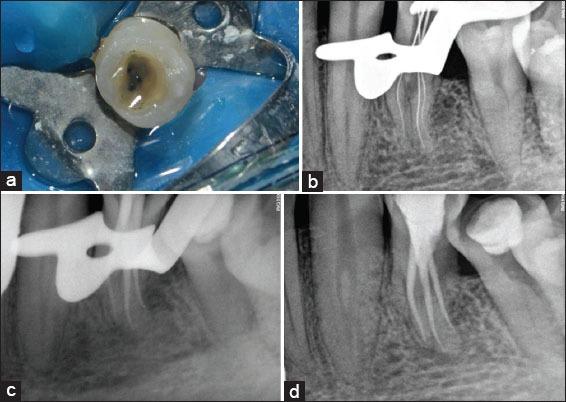

Understanding the morphological anatomy of the root and root canal systems of the teeth increases the success rate of endodontic therapy. Advanced diagnostic imaging techniques like cone beam computed tomography (CBCT) are an essential aid in understanding the anatomy of teeth especially in mandibular premolars. Most commonly mandibular first and second premolars have a single root and a single canal. However, multiple root and canals have also been reported. The present case report discusses endodontic management of a three rooted mandibular first premolar using CBCT.